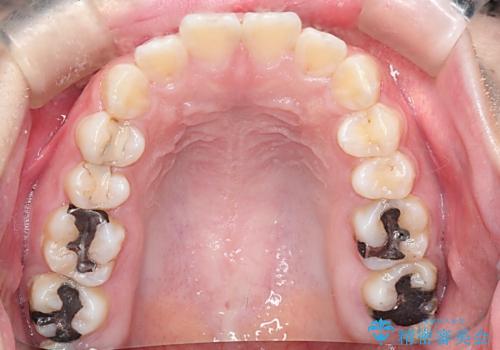

- 口元が出ていることを主訴に来院されました。

上下左右小臼歯を抜歯して審美装置で治療を行いました。

抜歯したスペースをきちんと下げることができるように、矯正用のアンカースクリューを用いて治療をしております。